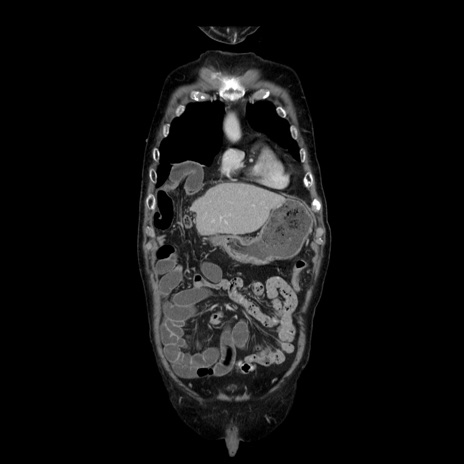

横断像

【症例】70歳代男性

【主訴】腹痛

【現病歴】肝硬変・肝細胞癌にてかかりつけの方。約9時間前に食後より腹痛出現。症状が徐々に増悪し、嘔吐出現したため来院。

【既往歴】肝硬変、肝細胞癌(RFA、TACE後)

【身体所見】意識清明、表情苦悶様、BT 36℃、BP 129/78mmHg、P 88bpm、SpO2 97%(RA)、右上腹部から心窩部にかけて圧痛あり、反跳痛なし、筋性防御あり。

【データ】WBC 5800、CRP 0.16